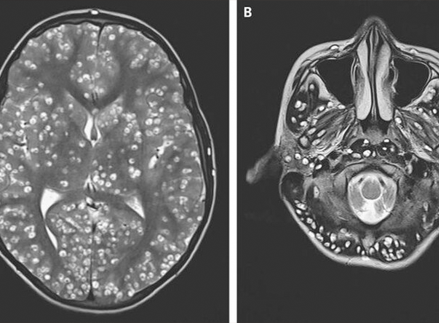

Otro caso que me impactó. El cerebro de un paciente de 49 años estaba completamente habitado por parásitos y sus larvas. El hombre falleció a causa de un infarto. ¡Pero esto es sólo una consecuencia! ¡En realidad, los parásitos simplemente se alimentaban del tejido cerebral humano, devorándolo vivo! Durante su vida, el paciente sufrió dolores de cabeza, tuvo trastornos del sueño y problemas de memoria. Luego, cuando muchas zonas ya estaban afectadas, se añadió la epilepsia.

He sido patólogo durante muchos años. ¡He visto cosas que nos ponen los pelos de punta! La gente subestima los riesgos, piensa que los parásitos son gusanos que viven en los intestinos. Pero no es así. Hay muchos tipos de parásitos. Por ejemplo, los hay diminutos, pero muy tóxicos. Envenenan su cuerpo, penetran en el torrente sanguíneo, el corazón, lo agotan con sus toxinas, provocan isquemia, insuficiencia cardíaca, hipertensión y, como resultado, ataques cardíacos y derrames cerebrales. ¡Se asientan en los pulmones, el hígado, penetran en el cerebro e incluso los órganos viven en los ojos!

Los representantes de los helmintos que afectan los órganos vitales son Taenia solium, echinococcus (Echinococcus granulosus), trichinella (Trichinella spiralis). Echinococcus es una etapa larval de un helminto del género Echinococcus. Y esto no es todo tipo de parásitos.